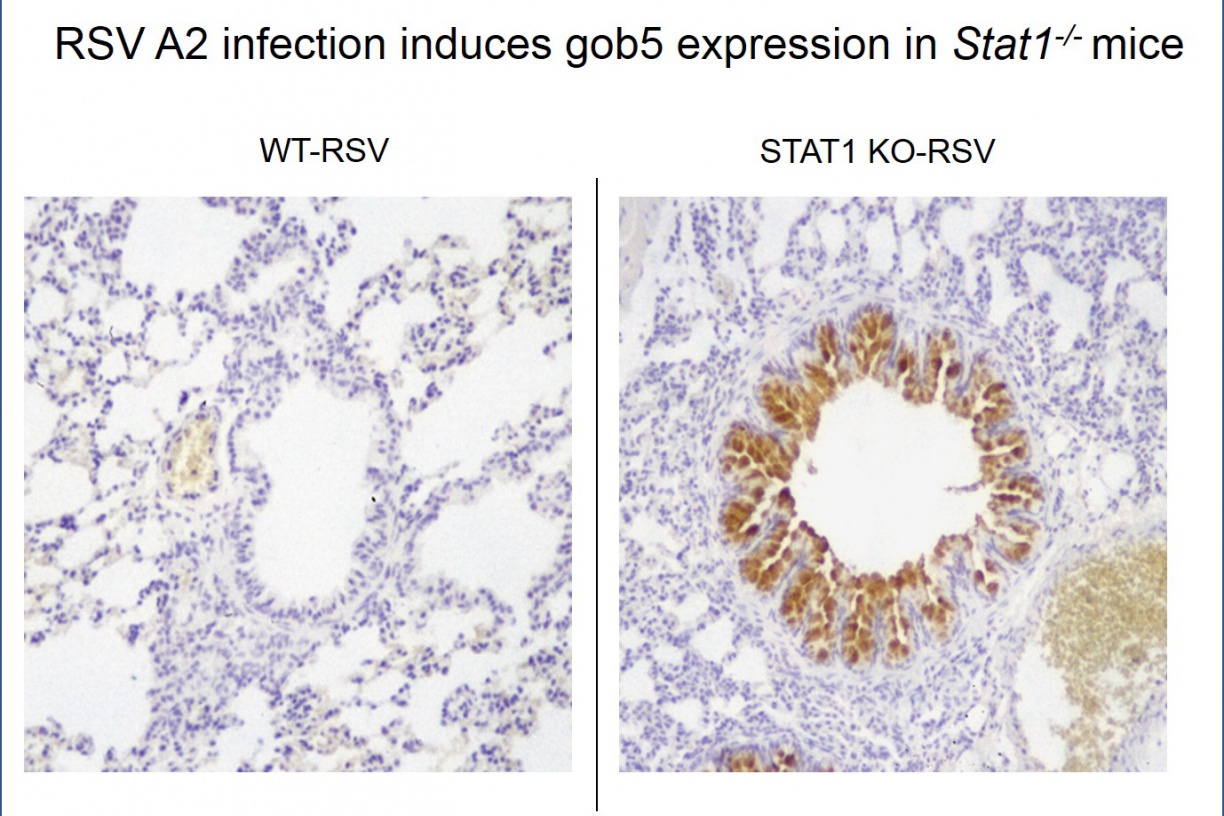

RSV Infection in the Setting of STAT1 Deficiency Increases Mucus Metaplasia and Airways Responsiveness

Aberrant Type 2 Responses to RSV Results in Airway Mucus

RSV A2 infection induces gob5 expression in Stat1 -/- mice.